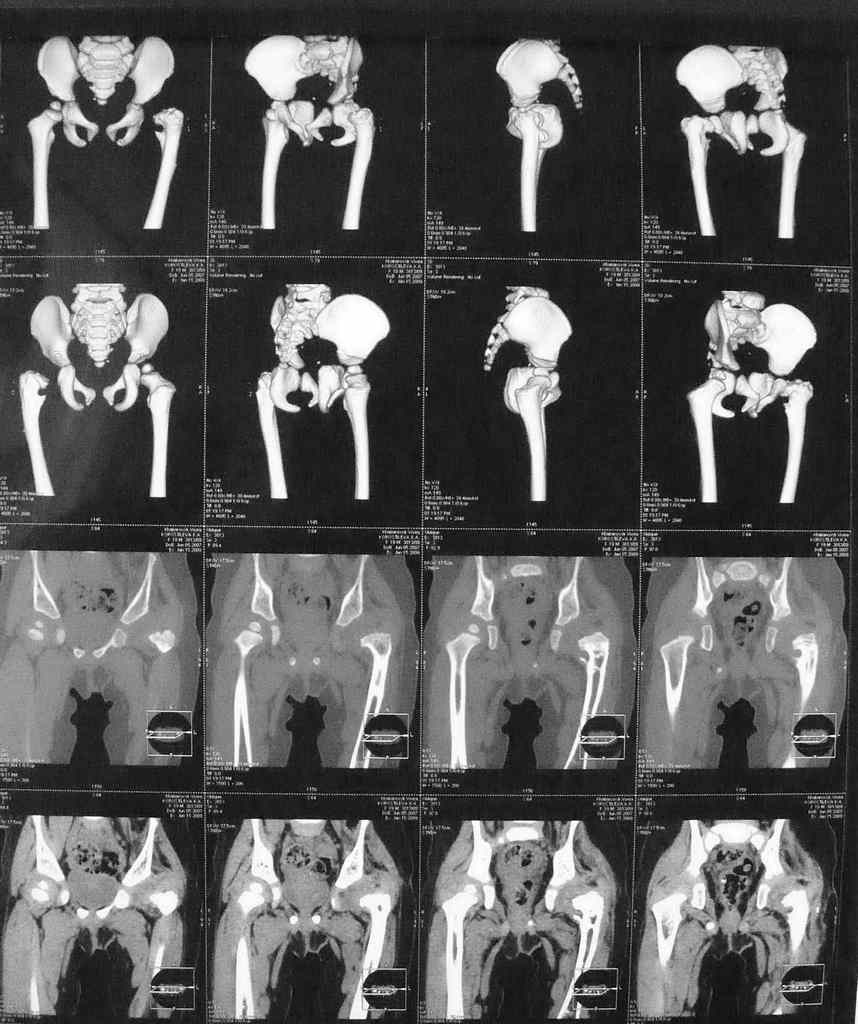

В 6 мес перенесла открытое вправление и деторсионную остеотомию с фиксацией.Через 9 мес фиксатор удален. Предлагается следующее вмешательство в обьеме варизирующей остеотомии. В прищепке КТ и 3Д реконструкция.Помогите советом кто в состоянии. Заранее благодарен. А Рыков

Naskolko moghno sudit po recontruction view of CT sleva sustav vpodvyvihe(subluxation),proximal femur in varus and avteversion, medial joint space widening isamoe glavnoe acetabular dysplasia.Obychno open reduction ne delaetsya vvozraste 6 mesyacev,dostatochno closed reduction +spica.

Vvashem sluchae varus osteotomy nichego putnogo ne dast.Prishlite obycnye AP +frog of pelvis, mo mne kaghetsya chto nughno sdelat : re open reduction, shortening of the femur +_ derotation +pelvic osteotomy.

Привет, А.Г.! По представленным КТ можно утверждать, что у ребенка асептический некроз головки бедра. ШДУ явно ниже нормы. Считаю, что в ближйший год нельзя вмешиваться на ТБС и, тем более, делать варизирующую остеотомию. Проведите активное ФТО (цель - улучшить кровоснабжение поясничного отдела позвоночника и ТБС). Постарайся в будущем не облучать ребенка на КТ, лучше МРТ. АИФ